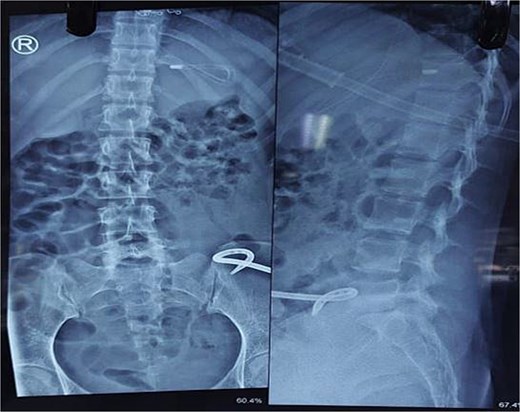

X-ray abdomen showed dilated small bowel loops with faecal loading (Fig. 1). Ultrasound abdomen/pelvis revealed dilated small bowel loops with to-and-fro peristalsis, suggestive of small bowel obstruction. Contrast-enhanced computed tomography (CT) abdomen/pelvis revealed distal ileal thickening causing obstruction, a left iliopsoas abscess communicating with a paravertebral abscess (L5–S2), and erosion of the L5 vertebral body (Figs 2 and 3).

X-ray abdomen showing dilated small bowel loops with faecal loading (erect and supine).